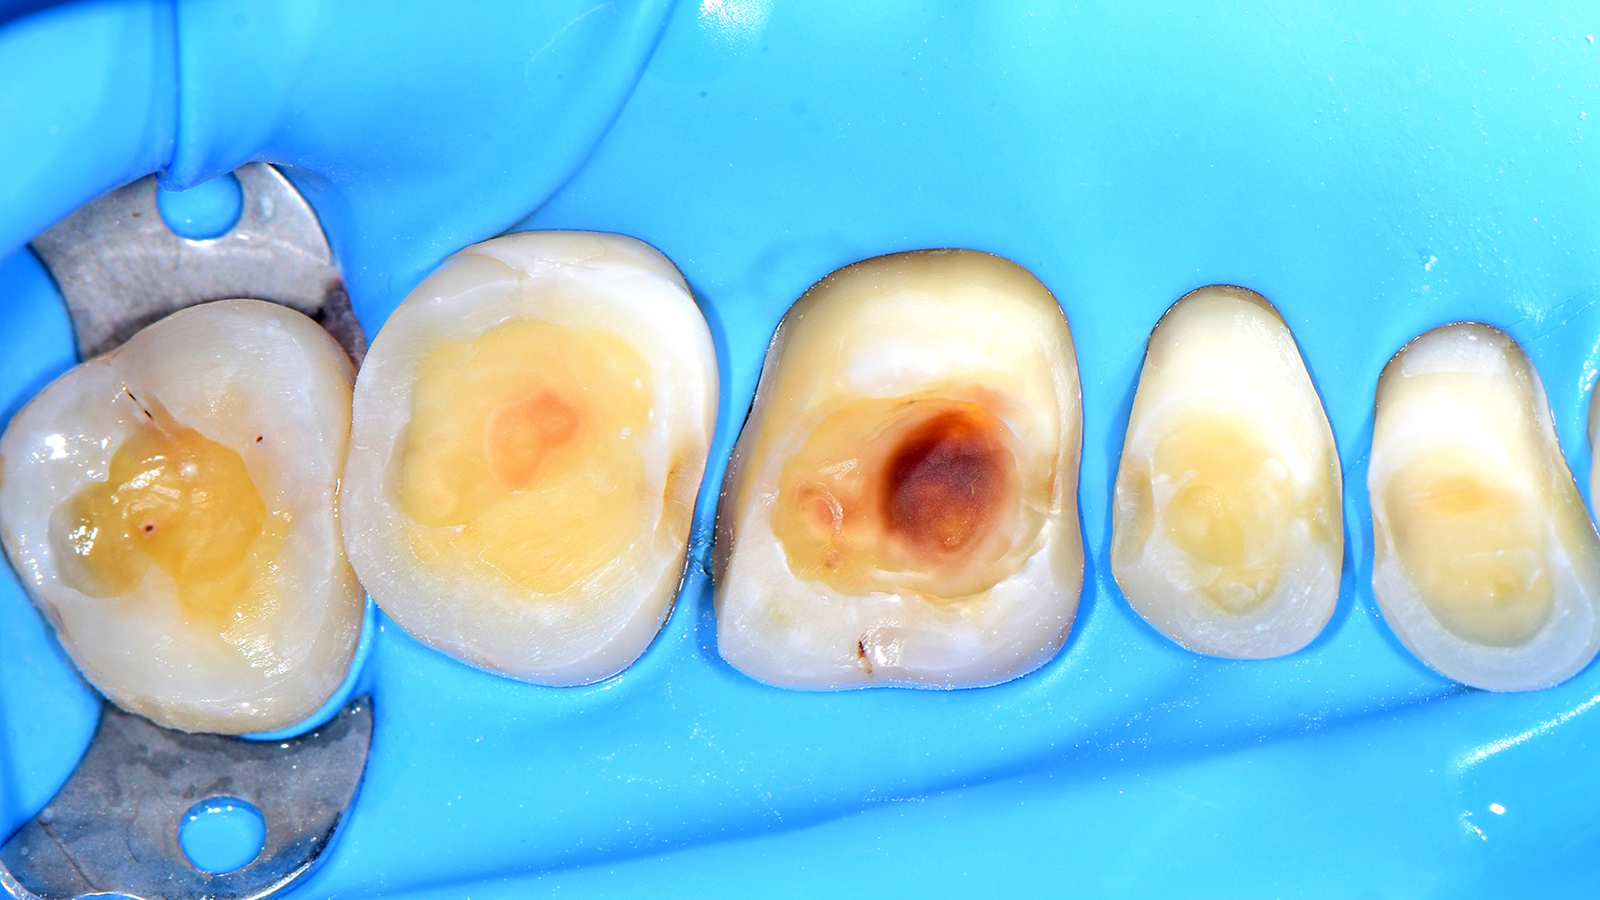

Does Charisma Bulk Flow ONE require an opaque blocker?

In case of severe discolourations, the tooth-coloured opaque shade Charisma Opal Flow OM (Opaque Medium) can be used. Alternatively, the white-opaque Charisma Opal Flow Baseliner can be used at the bottom of the cavity. This allows the coverage of discolourations and pre-vents the unnecessary removal of healthy tooth substance in case of a re-entry.

In an external study done by Prof. Nate Lawson Charisma Bulk Flow ONE was one of the materials which showed the highest depth of cure and at the same time the lowest translucency of the tested bulk fills. Charisma Bulk Flow ONE can be placed safely in up to 4 mm bulk layers without the need of an additional capping layer.